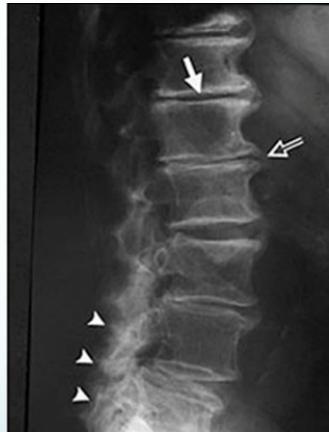

Radiographic Findings

- Narrowing of disc space

- Marginal bony spurs (Osteophytes)

- Osteoarthritic changes in facet joints